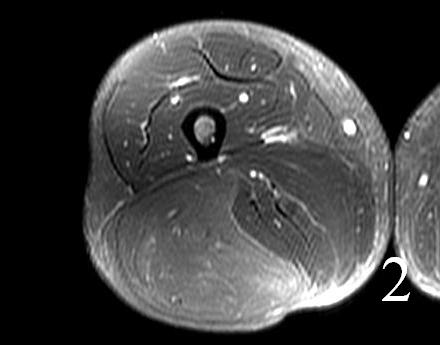

• High signal intensity similar to fat on T1W and T2W (Fig. 1 and 2)

Fig. 1-2 MRI of lower extremity hibernoma (Fig. 1 and Fig. 2) shows similar signal intensity to subcutaneous fat fat on different sequences.